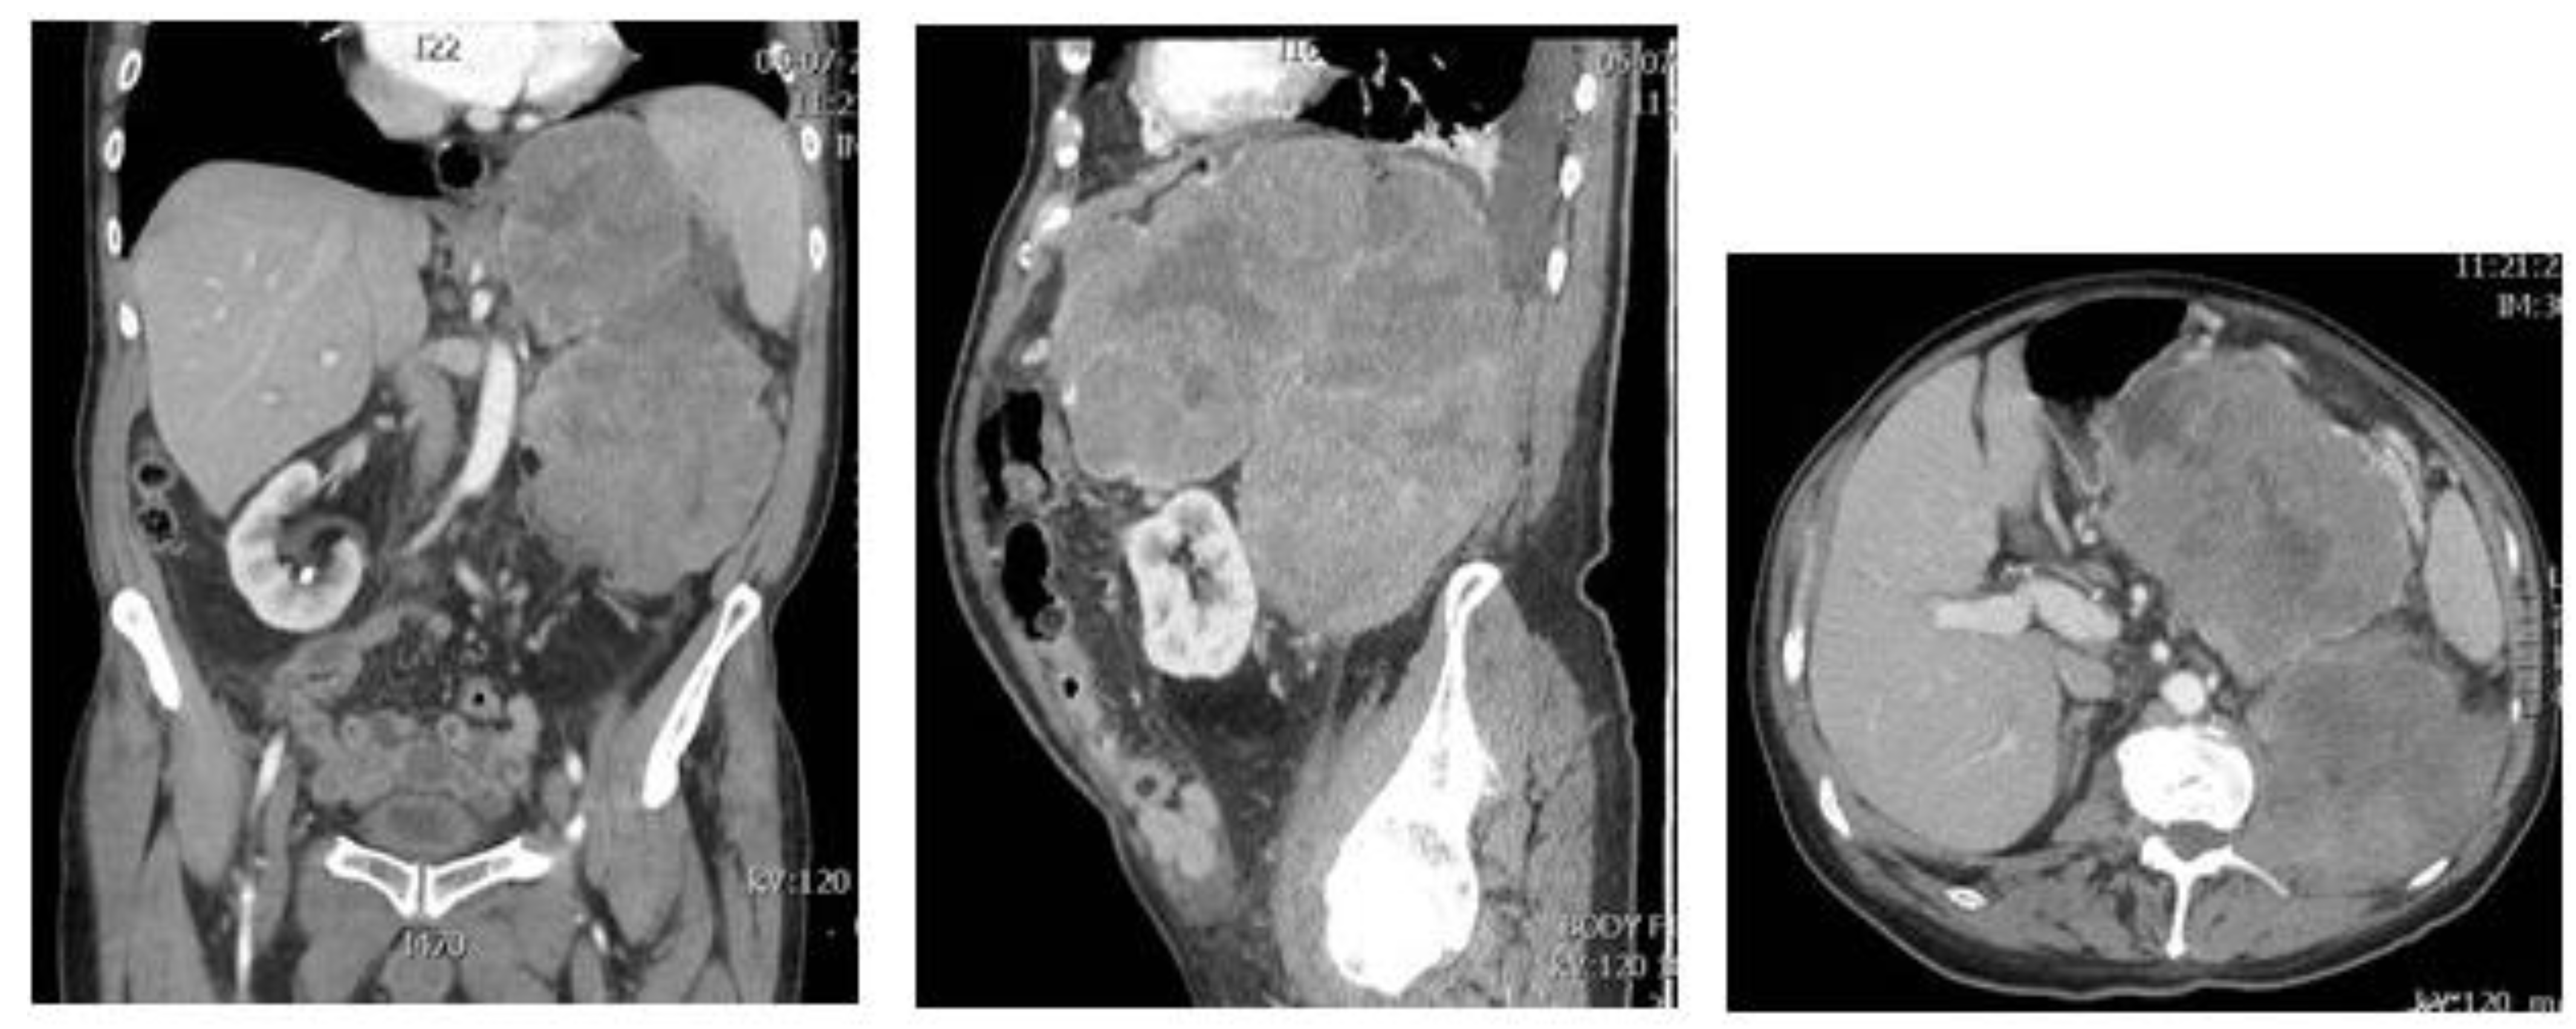

3. Dedifferentiated Liposarcoma